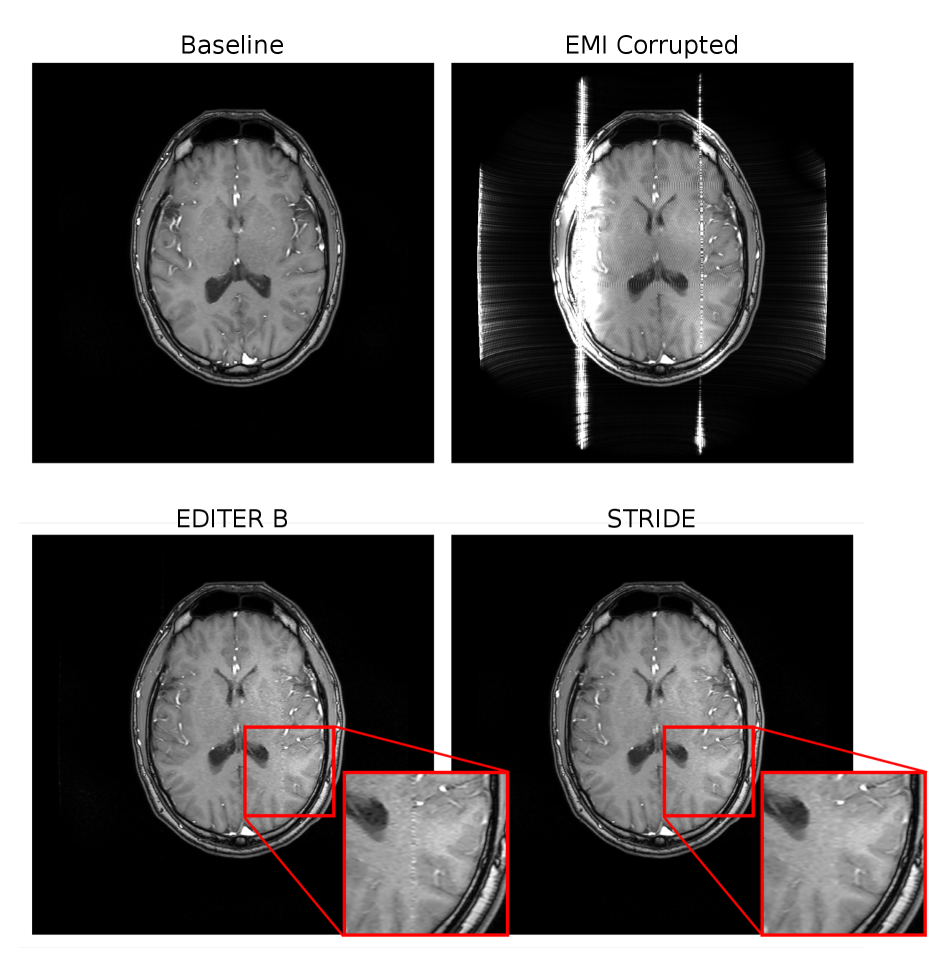

Figure 9. Visual comparison of the (top left) baseline, (top right) EMI corrupted, (bottom right) EMI corrected using STRIDE, and (bottom left) EMI corrected using EDITER B, which is the standard EDITER implementation given by Srinivas et al. [EDITER] for the 15-average in-vivo brain dataset. Channel combination was done using the vendor’s stock algorithm, which includes prewhitening, shading correcton, and unwarping. The EMI detectors were denoised using SVD-denoising. In the highlighted area, small artifacts from the narrow-band EMI can be seen in the EDITER B EMI corrected image, but not in the STRIDE EMI corrected image.